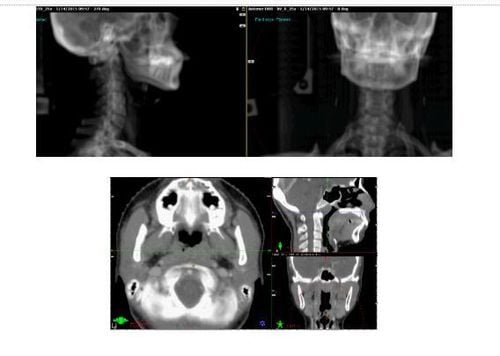

Hiện nay, chụp X-quang đóng vai trò rất quan trọng trong việc chẩn đoán và điều trị bệnh. Phương pháp này hỗ trợ bác sĩ quan sát bên trong cơ thể người bệnh mà không cần phải mổ. Bài viết dưới đây sẽ giúp chúng ta có thêm những hiểu biết đầy đủ nhất về chụp X-quang.

Can thiệp X quang thần kinh là kỹ thuật ngày càng được sử dụng rộng rãi trong chẩn đoán và điều trị các bệnh lý thần kinh trung ương. Phương pháp vô cảm đóng vai trò quan trọng trong việc tạo điều kiện thuận lợi để các thủ thuật X-quang thần kinh diễn ra suôn sẻ, mang lại cơ hội điều trị tốt cho bệnh nhân.